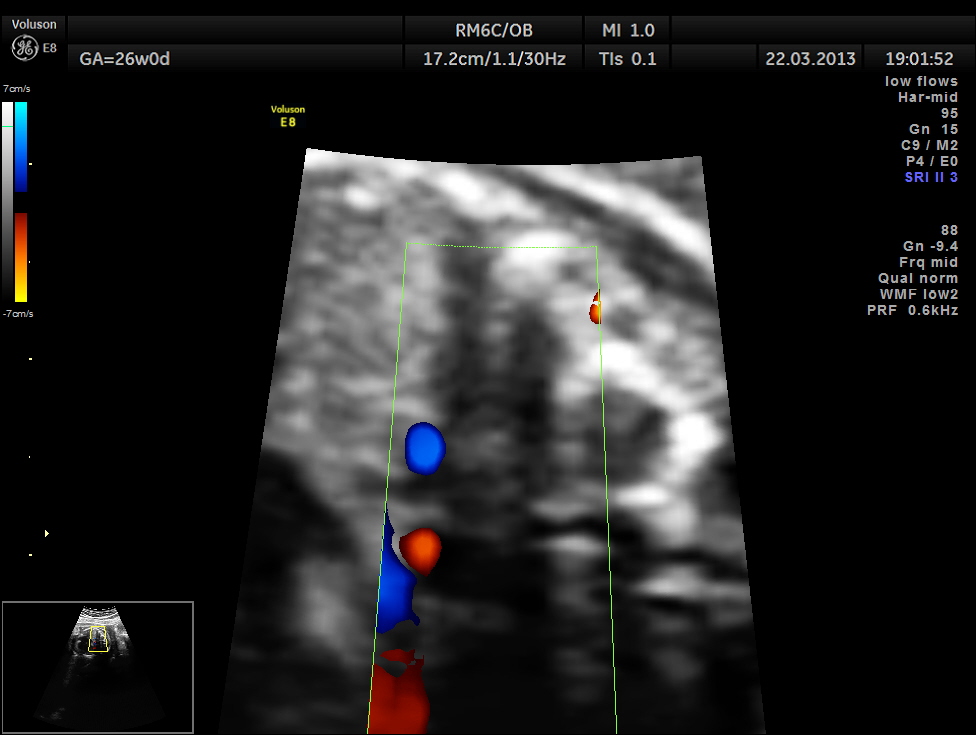

The next image shows spectral doppler showing prominent regurgitant jet in A V SEPTAL DEFECT